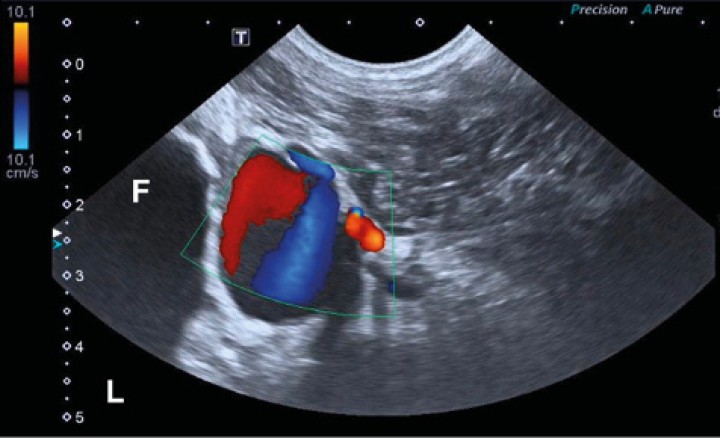

Se exploró ecográficamente la zona diafisaria del fémur derecho (Toshiba Xario 200, Canon Medical, Madrid) utilizando una sonda microconvexa con rango de frecuencias de 6 a 11 MHz. Se visualizó la lesión ósea descrita en otras pruebas. La cortical era irregular y discontinua, con un halo hipoecoico en el tejido blando. Junto a ella se halló una estructura hipoecoica redondeada y de pared fina (Fig. 4, video 1). La señal Doppler color de esta lesión era positiva con apariencia de remolino con color alternante rojo y azul (“signo de ying-yang”) (Fig. 5, video 2).

Figura 5

Imagen ecográfica en plano transversal con empleo de Doppler color en la región caudodistal de la diáfisis del fémur derecho. Se observa una estructura redondeada que produce un efecto de remolino en el Doppler color (signo “ying-yang”). “L”: lateral; “F”: fémur.

Con ecografía se puede identificar un aneurisma como una estructura de contenido anecoico íntimamente relacionada con un vaso arterial o venoso.3 En los aneurismas de origen infeccioso, se describen paredes engrosadas e hiperecoicas.4,5 En nuestro caso, la pared de la lesión era fina. Mediante ecografía Doppler en el aneurisma se identifica una potente señal de color con un patrón en remolino que suele describirse como con forma de “ying-yang”.3,6

Aunque la diferencia entre un aneurisma y un pseudoaneurisma es histopatológica, la identificación del cuello del aneurisma y el estudio del patrón de Doppler espectral permiten el diagnóstico del pseudoaneurisma. Con ecografía en 2D es difícil diferenciar un pseudoaneurisma venoso de uno arterial. Con Doppler pulsado en los pseudoaneurismas arteriales se observa flujo pulsado arterial y un espectro Doppler bidireccional de gran amplitud (llamado “to and fro”).6 La ecografía Doppler permite diferenciar la lesión de otras estructuras de aspecto similar en modo B, como estructuras quísticas o abscesos.2-3 En nuestro caso se diagnosticó el pseudoaneurisma mediante ecografía Doppler dúplex, pero no se realizó un estudio con Doppler pulsado que permitiera la diferenciación entre pseudoaneurisma arterial o venoso. La TC ayudó a clarificar que se trataba de un aneurisma venoso.